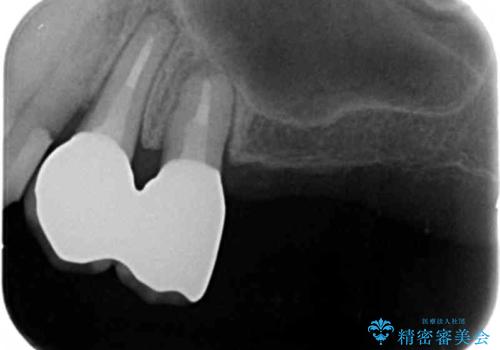

奥歯の違和感 再根管治療 40代女性

- 奥歯の違和感を主訴に来院された患者様です。

精査したところ、左上の大臼歯2本(左上67)が欠損しており、左上の小臼歯2本(左上45)は根が短く動揺があり根尖病変を認めました。

「大臼歯は入れ歯かインプラントを検討しているがまだやりたくないため、小臼歯のみを治療してほしい」との患者様のご希望により、

相談を重ねた上で小臼歯2本の再根管治療と連結補綴を行いました。

大臼歯がないため小臼歯に負担がかかりやすいことによるリスクを説明し、ご理解頂いた上で治療を行いました。